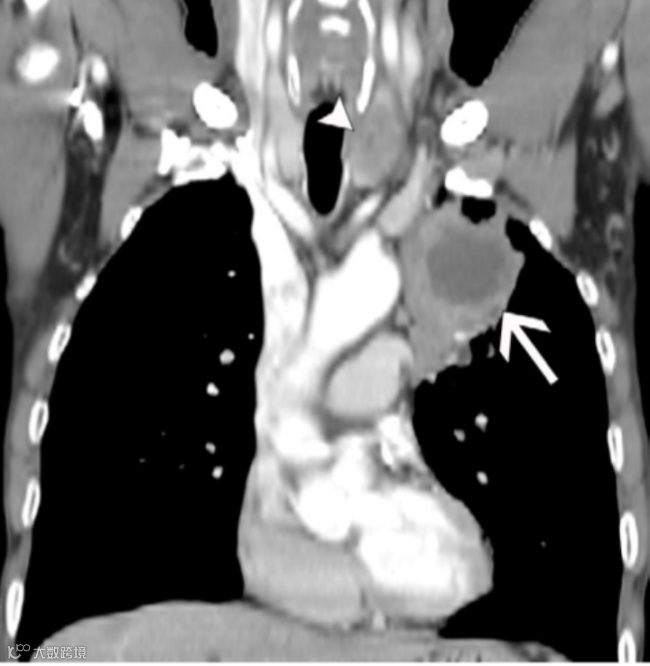

(A,B)63岁女性非小细胞肺癌(NSCLC)患者的冠状重建增强胸部CT图像(软组织窗)(A)显示左上叶原发肿瘤(箭头)直接侵犯左肺门,并且在对侧4R站点发现转移性N3淋巴结(短箭头)。与A图像相同水平的冠状融合FDG PET/CT图像(B)显示这些淋巴结(短箭头)呈FDG高摄取,类似于原发肿瘤(箭头)。